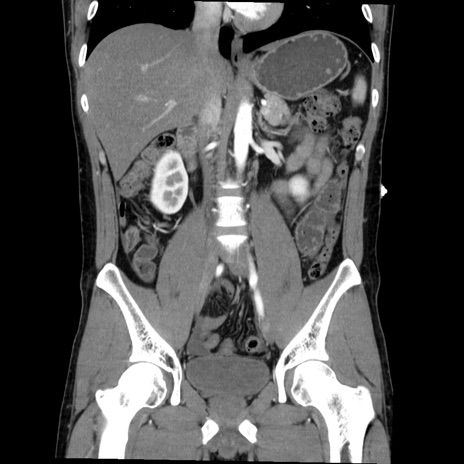

症例36(冠状断像)

【症例】20歳代 男性

【主訴】心窩部痛

【現病歴】今朝より上腹部痛あり。一旦軽快していたが再度出現したため救急要請。昨日夕に白身の魚を含む刺身を食べた。

【身体所見】BP 136/89mmHg、HR 74/min、BT 37.0℃、腹部:膨満、軟、心窩部に圧痛あり。反跳痛なし、筋性防御なし、腸雑音やや亢進あり。

【データ】WBC 17700、CRP 0.48